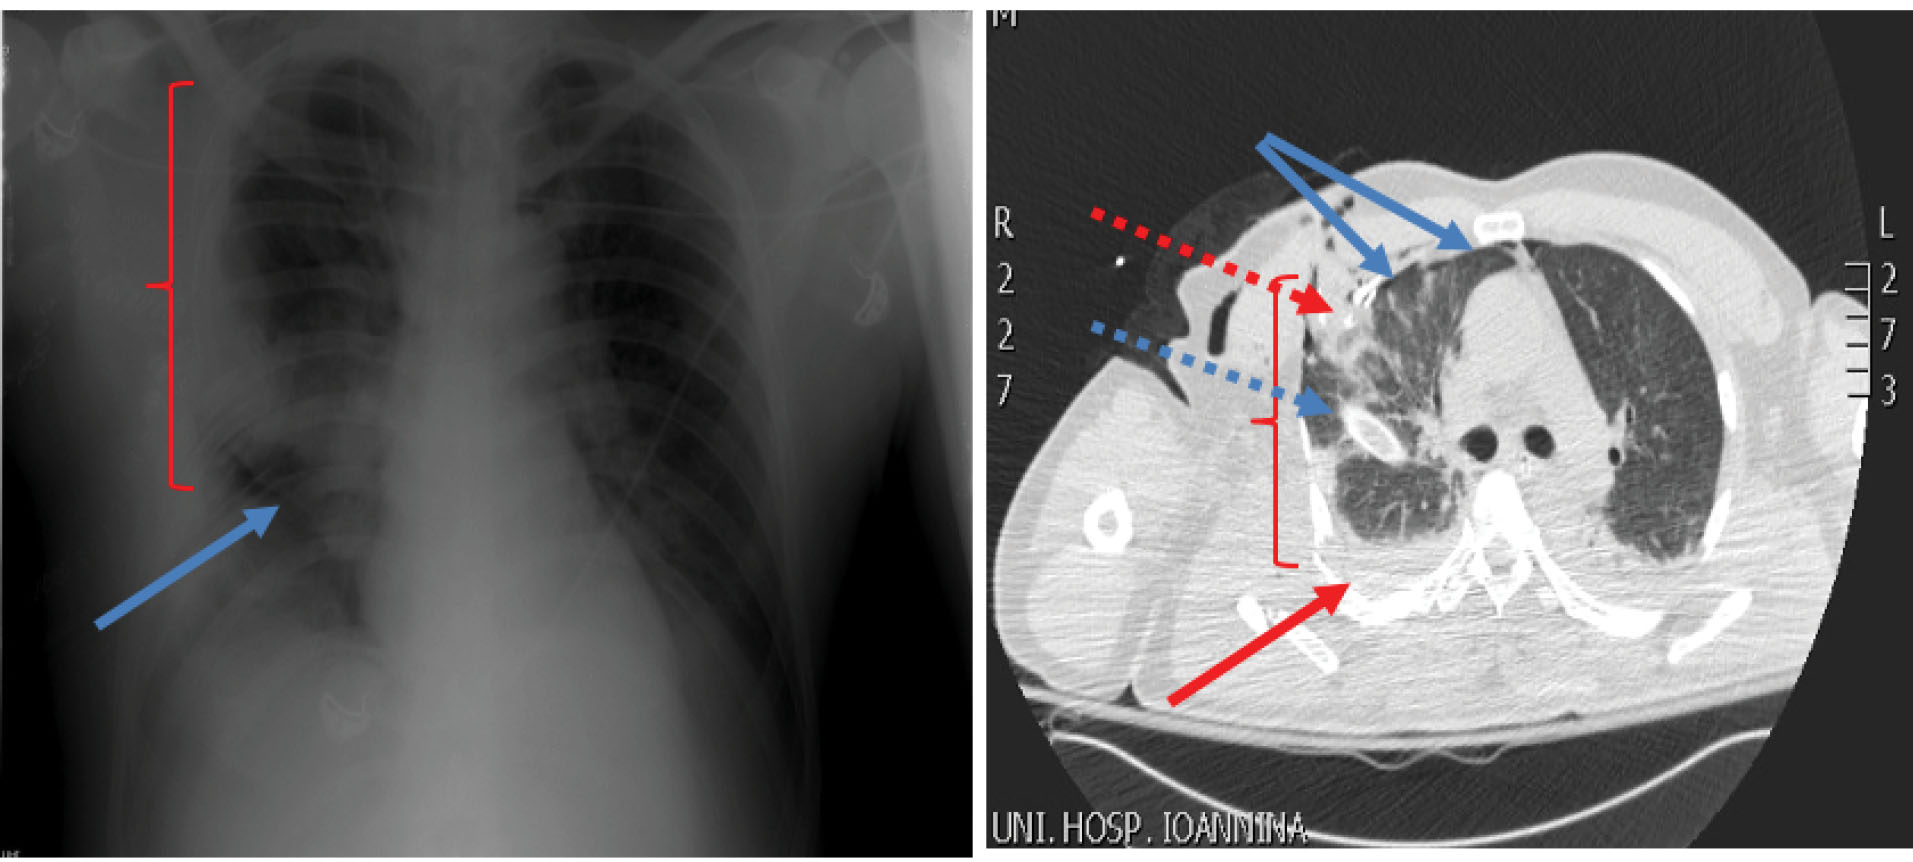

A 58-year-old patient, who was an excavator operator, was crashed down by the bucket of the excavator during work time. His injury resulted in right ribs comminuted fractures and in three infected penetrating traumas of his right anterolateral chest wall. The patient was transferred to hospital having hypoxia and air and blood leak from open wounds, though being hemodynamically stable (blood pressure=110/65 mm Hg, heart rate = 90 beats per minute (bpm)). Physical examination proved neither additional injuries nor any change in Glasgow Coma Scale. Chest x-ray showed right pneumothorax and hemothorax, severe pulmonary contusion of the right lung and multiple rib fractures from the second rib to the eighth one (). Subsequently, a chest tube was placed in his right hemithorax. Arterial blood gases showed severe hypoxia (PO2 = 58 mm Hg, PCO2 = 31 mm Hg, SatO2 = 88%). The patient was intubated and transferred to the operating theatre, where the presence of rib fractures from the second to the eighth rib and of three lung rupture sites with massive air leak were noticed. Debridement of chest wall traumas, suturing of lung rupture sites with a continuous 4-0 Prolene suture through a right lateral thoracotomy and drainage of right pleural cavity via a wide chest tube were performed (). During next postoperative week, the patient presented serious hypoxia and paradoxical motion of the anterolateral chest wall. Despite ventilatory support with FiO2 of 70%-80% and positive end expiratory pressure of 15 mm Hg, patient’s oxygenation was affected (PO2 = 62 mm Hg, PCO2 = 36 mm Hg, SatO2 = 90%) and his extubation was impossible. Consequently, stabilization of chest wall was decided on the seventh postoperative day. After patient’s sedation, two reusable malleable, metallic bars, 25 and 30 centimeters long were chosen and sutured crosswise, so as complete contact with the mobile part of the anterolateral chest wall to be achieved. Multiple non-ischemic, interrupted, 2-0 Nylon sutures were used suturing the bars on the patient’s skin and subcutaneous layer and between them. The edges of metallic bars were sutured on the adjacent normal, stable chest wall resulting in apparent limitation of paradoxical motion (). After chest wall stabilization, arterial blood gases were clearly improved. (PO2 = 75 mm Hg, PCO2 = 36 mm Hg, SatO2 = 96%) Respiratory function improved, hypoxia regressed and the patient was successfully extubated on the third post-stabilization day having satisfactory air blood gases and chest x-ray (). Lung contusion resolution along with mechanical stabilization of the chest were probably the contributors of this achievement. External metallic bars were removed on the ninth post-stabilization day, without any sign of skin necrosis, by simply dividing the stabilizing non-ischemic sutures. The patient was discharged on the 16th post-stabilization day in good health condition without paradoxical motion of his chest wall (). An informed consent was obtained from the patient for the publication of this data.

Figure 2. External stabilization with metallic bars a) Two reusable, malleable, 25 and 30 centimeters long, metallic bars were sutured crosswise in complete contact with the mobile part of the anterolateral chest wall. The edges of metallic bars were sutured on the adjacent normal, stable chest wall; b) Improved chest x-ray on the third post-stabilization day; c) Chest x-ray on patient’s discharge)